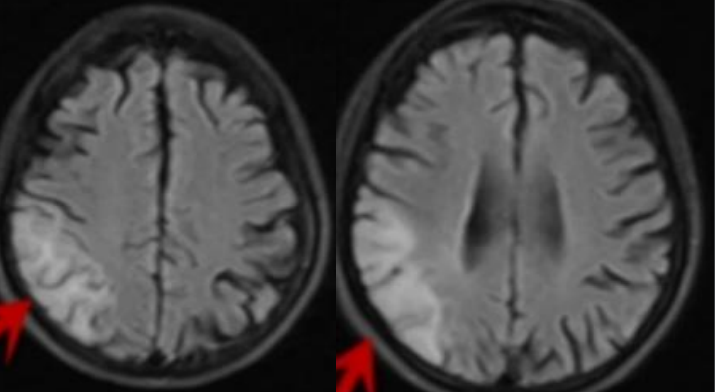

61岁男患,癫痫。2014年头MRI如下:

2020年头MRI如下:

答案:脑淀粉样血管病相关炎症(CAA-RI)。多呈急性或亚急性起病,最常见的表现是认知及行为改变,可表现为不同程度的痴呆、幻觉、人格改变、意识障碍甚至昏迷,其次是偏瘫、偏身感觉障碍、失语、共济失调等局灶性神经功能受损表现。另外,以癫痫、头痛等症状起病的患者亦不在少数,而相比单纯CAA而言,颅内出血的发生率则较低。MRI上最常见的表现为软脑膜明显强化及T2WI或FLAIR上的皮质下白质高信号灶,病灶常为非对称性,可散在分布或融合成片,灰质较少累及。